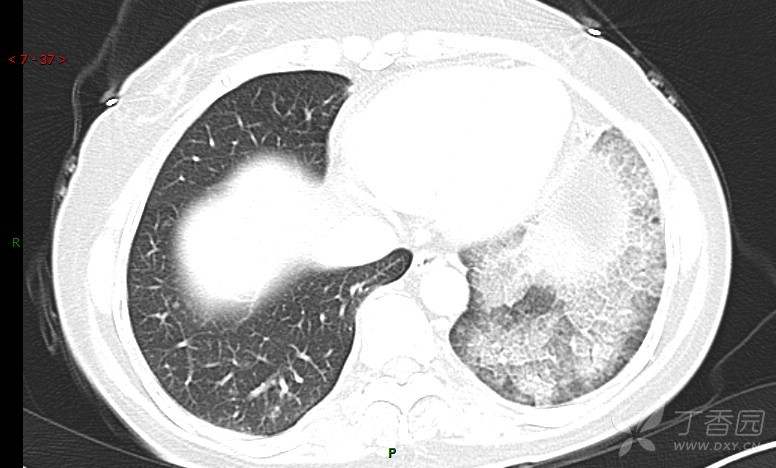

腺泡结节影,蜂窝征,这些都在提示……(病例3连发,附其他2例链接,病理已公布)

咳嗽1年余,加重7天。

患者于1年余前始受凉后出现咳嗽,多为干咳,未在意,未到医院就诊。近3月患者出现咳痰,多为黄色粘痰,量大,伴乏力,偶有头晕、心慌,无发热、胸痛、憋喘,无低热、盗汗、咯血、胸痛,无头痛,无恶心、呕吐、腹痛、腹泻,无尿频、尿急、尿痛,在当地诊所给予抗感染等对症支持治疗(具体药物及剂量不详),症状仍时有反复。患者于1月余前到外院就诊,行胸部CT提示双肺炎症,左肺重,考虑为“间质性肺炎”,给予“左氧氟沙星、利巴韦林、头孢哌酮舒巴坦钠注射液”治疗,复查胸部CT示病灶吸收不理想,后出院继续于诊所对症治疗(具体药物及剂量不详),效果欠佳。7天前患者无明显诱因出现上述症状加重,为求进一步诊治,特来我院就诊,我院门诊以“肺炎(重症)?”收入留观室,留观室给予“盐酸莫西沙星氯化钠”等对症治疗后,今日转入我科。患者自发病以来,神志清,精神差,饮食正常,睡眠增多,大小便正常,体重近3月减轻5公斤余。